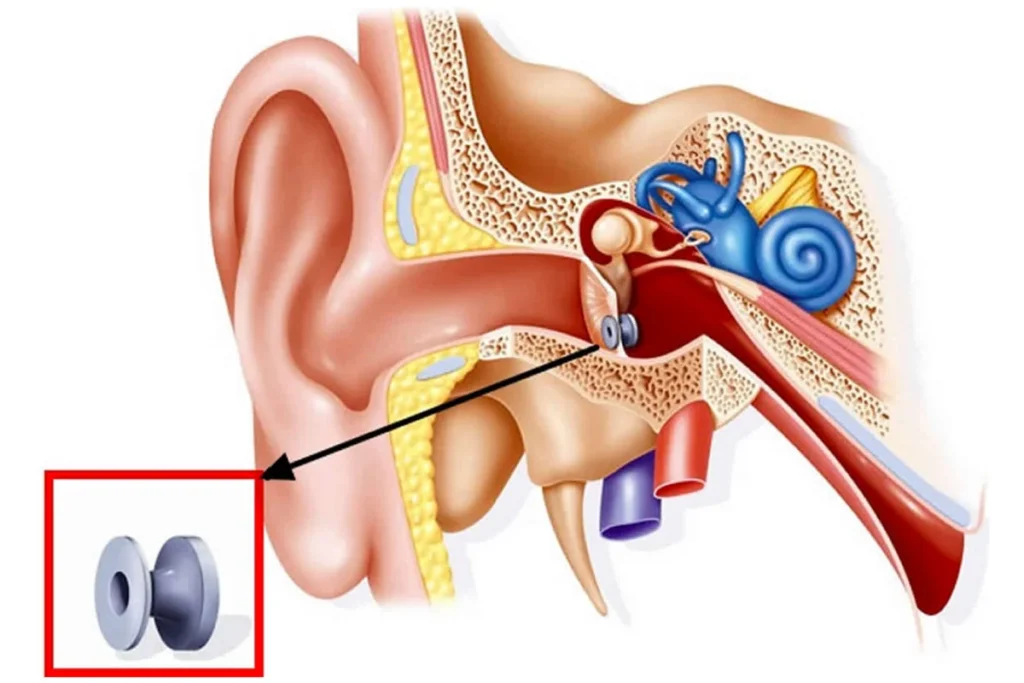

Akut orta kulak iltihabı, özellikle çocukluk çağında…